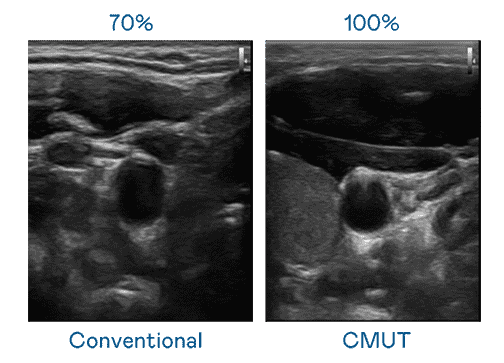

CMUT 技术是一种用电容式微机电元件来产生超音波讯号的技术。。。。与传统 PZT 压电式技术相比,,CMUT 频宽增加 30%,,更宽频的超音波讯号让影像解析度大幅提升,,,,是实现高影像品质医疗超音波扫描、、、促进精准医疗发展的关键技术。。。。

超音波影像的解析度高低,,,,首先取决于探头能发出的讯号频宽。。。。尊龙集团 CMUT 可提供高清晰的超音波讯号,,,,提供高频宽、、高灵敏度、、影像纹理细节更高的超音波影像,,协助医护人员缩短影像判读时间及利用精准的医疗影像进行诊断。。